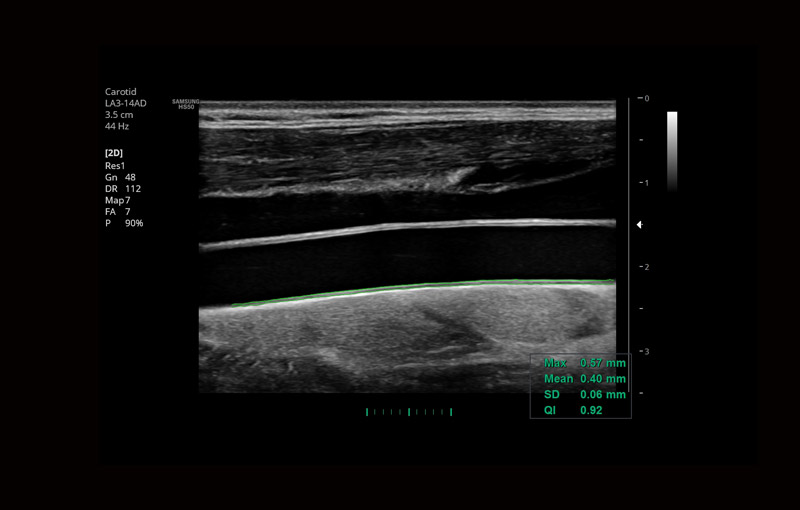

Dentre os exames de ultrassonografia, os exames Doppler se caracterizam por avaliar de forma específica detalhes do sistema circulatório, de forma não invasiva, ou seja, sem uso de medicamentos, meios de contraste, sem uso de radiação, e sem necessidade de sedação ou internação hospitalar, de forma indolor e sem efeitos colaterais, podendo ser realizado inclusive em gestantes para avaliação do bem estar do feto. Um dos principais benefícios dos exames Doppler é justamente a avaliação da saúde fetal, quando o médico examina principalmente as artérias do cérebro fetal, do cordão umbilical e também as artérias uterinas. Com base nos dados obtidos, é possível prever, por exemplo, a chançe da gestante desenvolver hipertensão gestacional, bem como se o feto está recebendo pelo cordão umbilical a oxigenação necessária, ou se há algum sinal sugestivo de redução da oxigenação cerebral. Algumas vezes pode ser preciso, caso a circulação fetal esteja muito comprometida, realizar o parto antes da data prevista, e o exame Doppler obstétrico é fundamental para auxiliar na decisão da melhor hora para a intervenção do médico obstetra. Nas áreas de cardiologia, neurologia e cirurgia vascular, a aplicação do exame Doppler é ampla. Os exames mais realizados são o Doppler de carótidas e vertebrais (artérias da região do pescoço que cursam para o cérebro), e o doppler de membros inferiores, tanto para avaliação de trombose, varizes e redução da circulação arterial. Nesses casos, o exame auxilia o médico assistente na análise de placas ateromatosas (depósitos de colesterol e calcificações), bem como se o fluxo sanguíneo está suficiente ou insuficiente para os órgãos específicos, ou ainda se há alguma trombose venosa ou oclusão das artérias. No caso das varizes, o exame detalha a anatomia venosa, bem como onde a causa das veias dilatadas se inicia, as veias insuficientes, o trajeto varicoso, e é fundamental para o planejamento e escolha da técnica cirúrgica, reduzindo de forma significativa o índice de recidivas e complicações pós-operatórias. O exame Doppler é também realizado na diferenciação de lesões de outros órgãos, como na tireóide e na mama, e tem grande importância na avaliação de órgãos pré e pós transplantes, como por exemplo do fígado e dos rins.